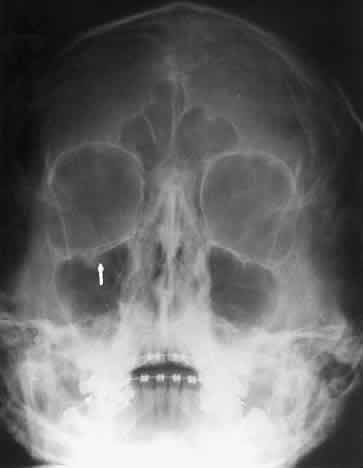

The optic foramen should measure 6 mm vertically and 5 mm horizontally. Asymmetry greater than 1 mm or a vertical dimension greater than 6.5 mm is considered abnormal.15,27 Ninety-eight percent of patients have optic canals that vary by less than 1 mm.27 Concentric enlargement of the foramen and optic canal can be seen with optic nerve gliomas, meningiomas, neurofibromatosis, and less commonly an aneurysm of the ophthalmic artery (Fig. 16). A decrease in the optic foramen and canal dimension can be seen in fibrous dysplasia, Paget's disease, hyperostosis secondary to a meningioma, or microphthalmos (Fig. 17, Table 1).

Fig. 17. Bilateral optic canal compression from fibrous dysplasia. There is diffuse bone thickening in each orbit. Note small size of optic foramen (arrow).